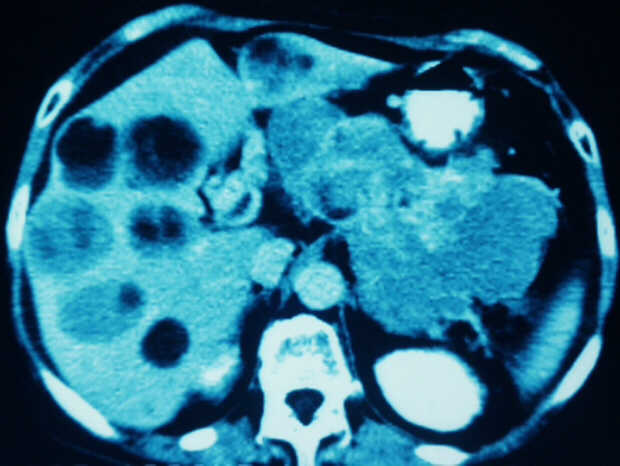

Pancreatic Head Mass: What Can Be Done?

Diagnosis: Angiography